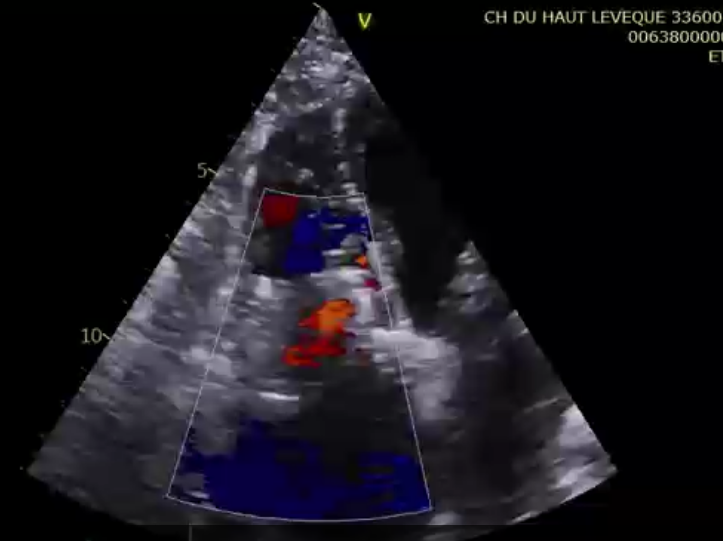

第一名患者是一位83歲的女性,術(shù)前TTE診斷TR等級4+,既往有高血壓和持續(xù)性房顫的病史。術(shù)者通過右頸靜脈入路的方式將輸送系統(tǒng)送入右心房,在DSA和TEE的引導(dǎo)下對輸送系統(tǒng)進(jìn)行調(diào)彎和推送,將輸送系統(tǒng)送至右心室目標(biāo)位置,接著調(diào)整其同軸性,使輸送系統(tǒng)在多個(gè)超聲引導(dǎo)平面下都垂直于三尖瓣瓣環(huán)。隨后開始釋放主體支架,錨定片與夾持件放出后,在TTE的引導(dǎo)下確認(rèn)了兩個(gè)夾持件分別在三尖瓣前葉和后葉的瓣下,且支架整體深度合適后,術(shù)者完整地釋放出整體支架。術(shù)者在DSA和TEE引導(dǎo)下確認(rèn)了錨定片完美貼合室間隔,再次確認(rèn)了瓣膜位置與同軸性良好后,通過獨(dú)有的錨定針將錨定片與室間隔固定,接著將瓣膜與輸送系統(tǒng)解離,完成手術(shù)。術(shù)后即刻瓣膜形態(tài)穩(wěn)定,輕微反流殘留,反流下降2+以上?;颊咝g(shù)后七天復(fù)查,經(jīng)胸超聲檢查提示患者右心功能明顯改善,僅可見輕微反流。

術(shù)前超聲提示極大量三尖瓣反流